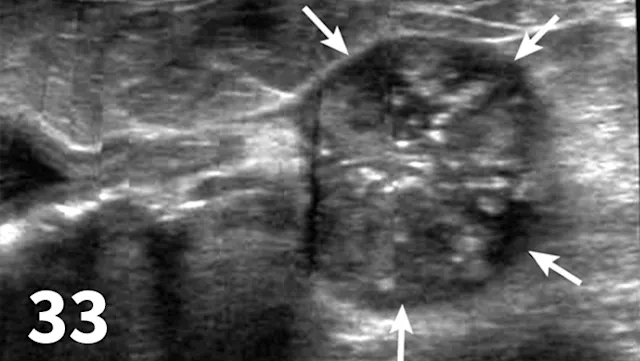

Prostate Gland

Survey radiography can be used to evaluate the size, shape, and opacity of the prostate gland (Figures 31 and 32). Ultrasonography has the advantage of providing tissue-architecture information. Prostatic abscesses, internal cysts, and paraprostatic cysts are readily visualized on ultrasonography. Ultrasonography can also aid in diagnosing benign hyperplasia (homogenous echotexture with intact capsule) and prostatic neoplasia (heterogenous with course echotexture and irregular margins) (Figure 33) and with identifying any potential source of excess androgen production (eg, adrenal glands, retained testes) in cases of suspected squamous metaplasia of the prostate gland. Mineralization of the prostate in a neutered dog is suggestive of neoplasia and can be detected by both survey radiography and ultrasonography. Sublumbar lymph nodes can also be evaluated by ultrasonography, whereas radiography is best for evaluating the adjacent lumbar spine (Figures 34 and 35).